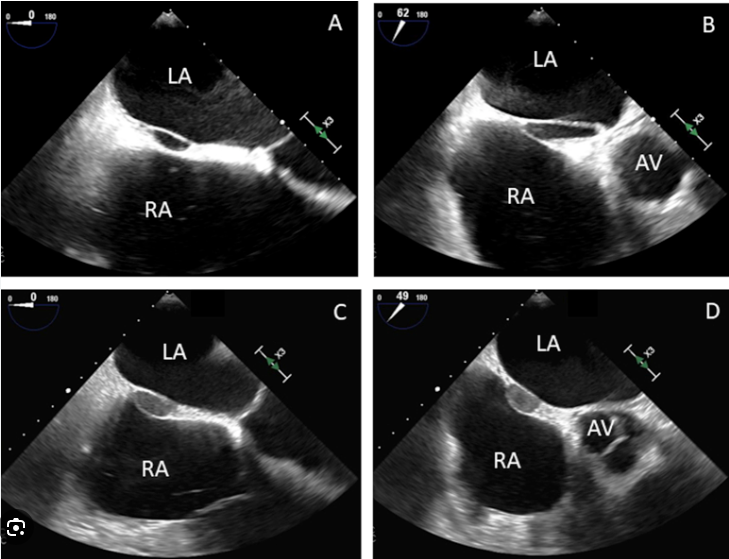

| 심방 중격 파우치 (Septal Pouch, SP) 란 심장의 좌심방과 우심방 사이에 위치한 심방 중격 (interatrial septum) 에 형성되는 주머니 모양의 공간을 말합니다. 이는 심방 중격의 해부학적 변이 중 하나로, 정상적인 심장 구조에서는 나타나지 않습니다. 형태:

| 좌측 SP는 76마리(95%)의 고양이에서 발견되었으며, 우측 SP는 23마리(29%)에서 발견되었습니다. |